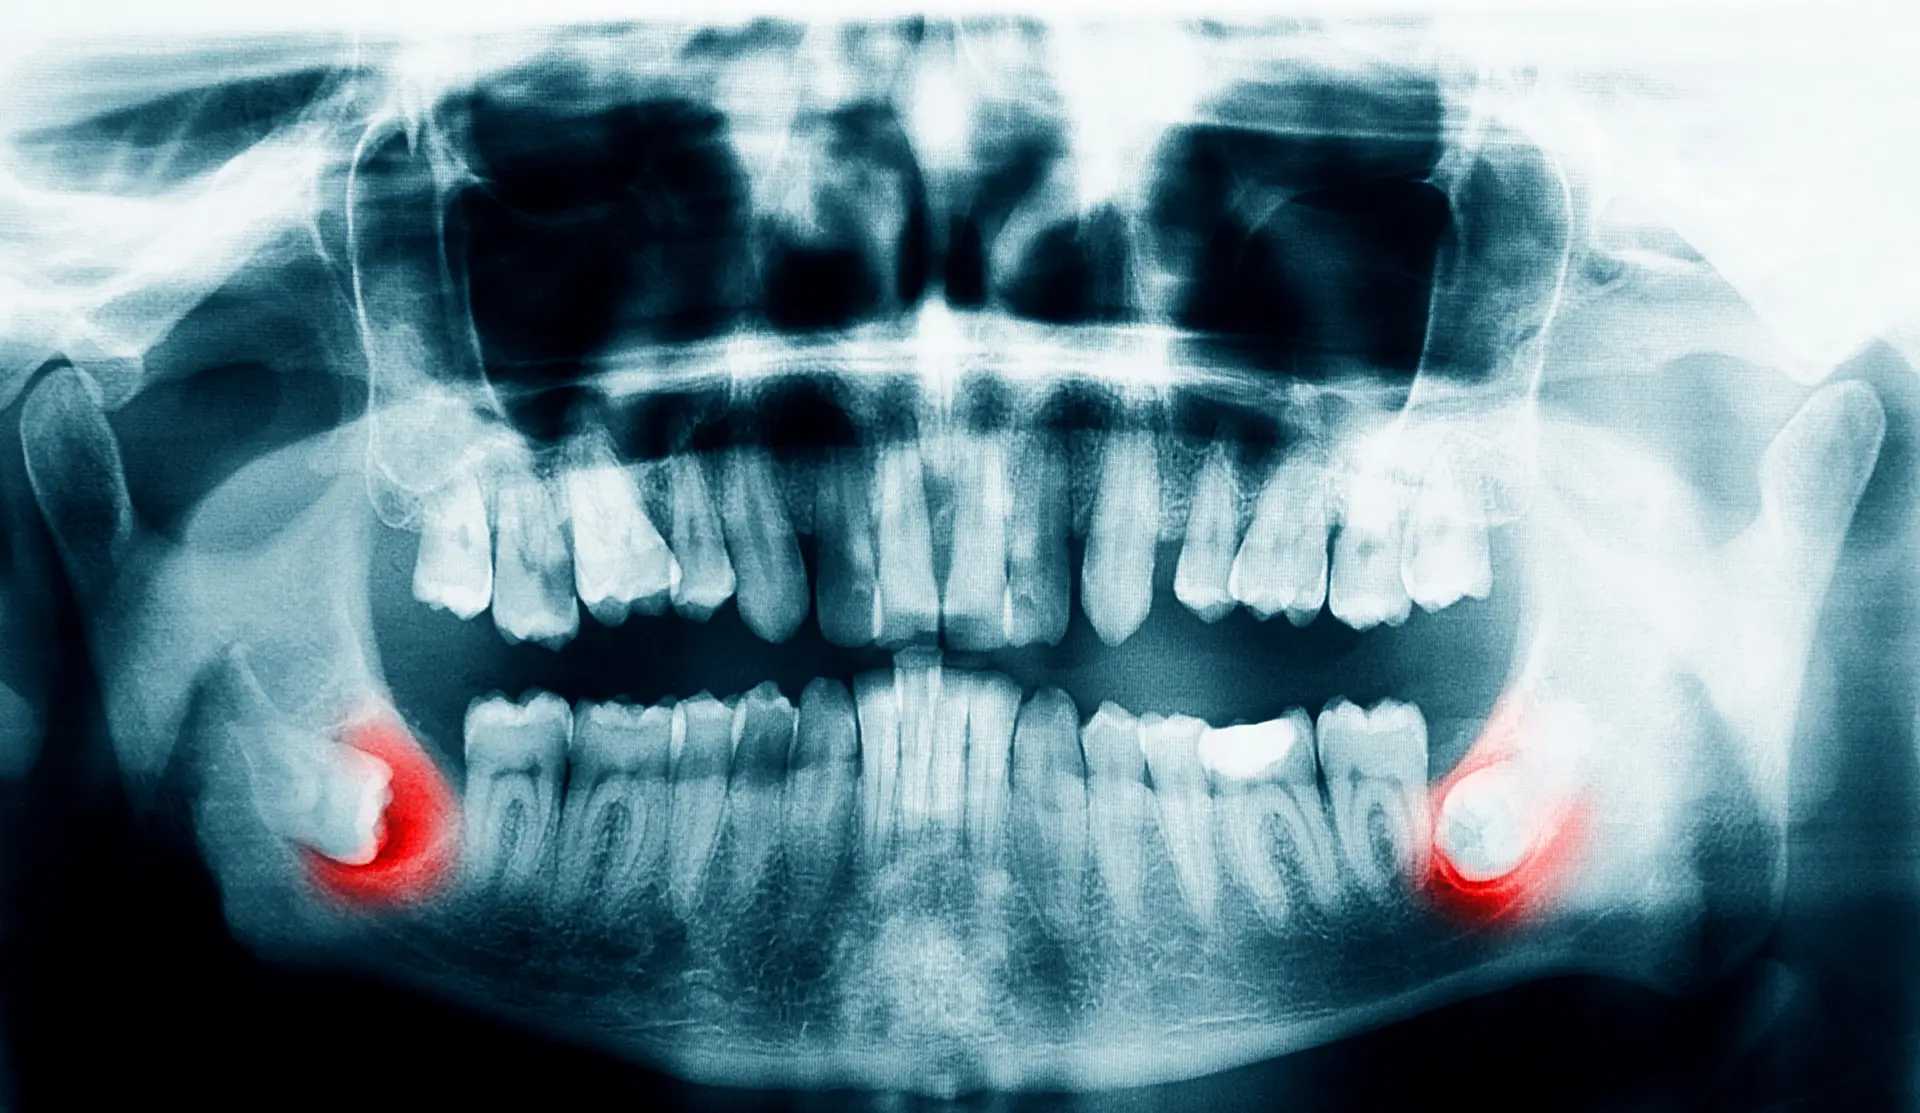

Digital x-rays provide high-resolution images of your teeth which allows us to make more precise diagnoses. We can see exactly why the tooth is causing pain and determine if an extraction is needed.

Wisdom teeth often have to be extracted to ensure the rest of your teeth stay healthy. Most wisdom teeth erupt misaligned, which can cause tooth crowding and disruption in your teeth and gums. This is not only painful but can make oral hygiene more difficult. Another common reason for wisdom teeth extraction is a partial eruption. This encourages bacteria to accumulate in the pockets of your gums, putting you at risk for gum disease, infection, and tooth decay. That being said, sometimes wisdom teeth don’t always need to be removed. If your wisdom teeth erupt properly aligned and don’t impact your other teeth, your doctor may not recommend extraction. But generally, wisdom teeth need to be removed to preserve a healthy smile.

There are many reasons why wisdom teeth removal may be necessary. This includes wisdom teeth growing in at the wrong angle. They can grow sideways, partially erupt, or even become trapped underneath the gum and bone. Impacted wisdom teeth can take many positions in the bone as they try to find a pathway to successfully erupt. All of these reasons make wisdom teeth removal necessary to preserve your oral health.